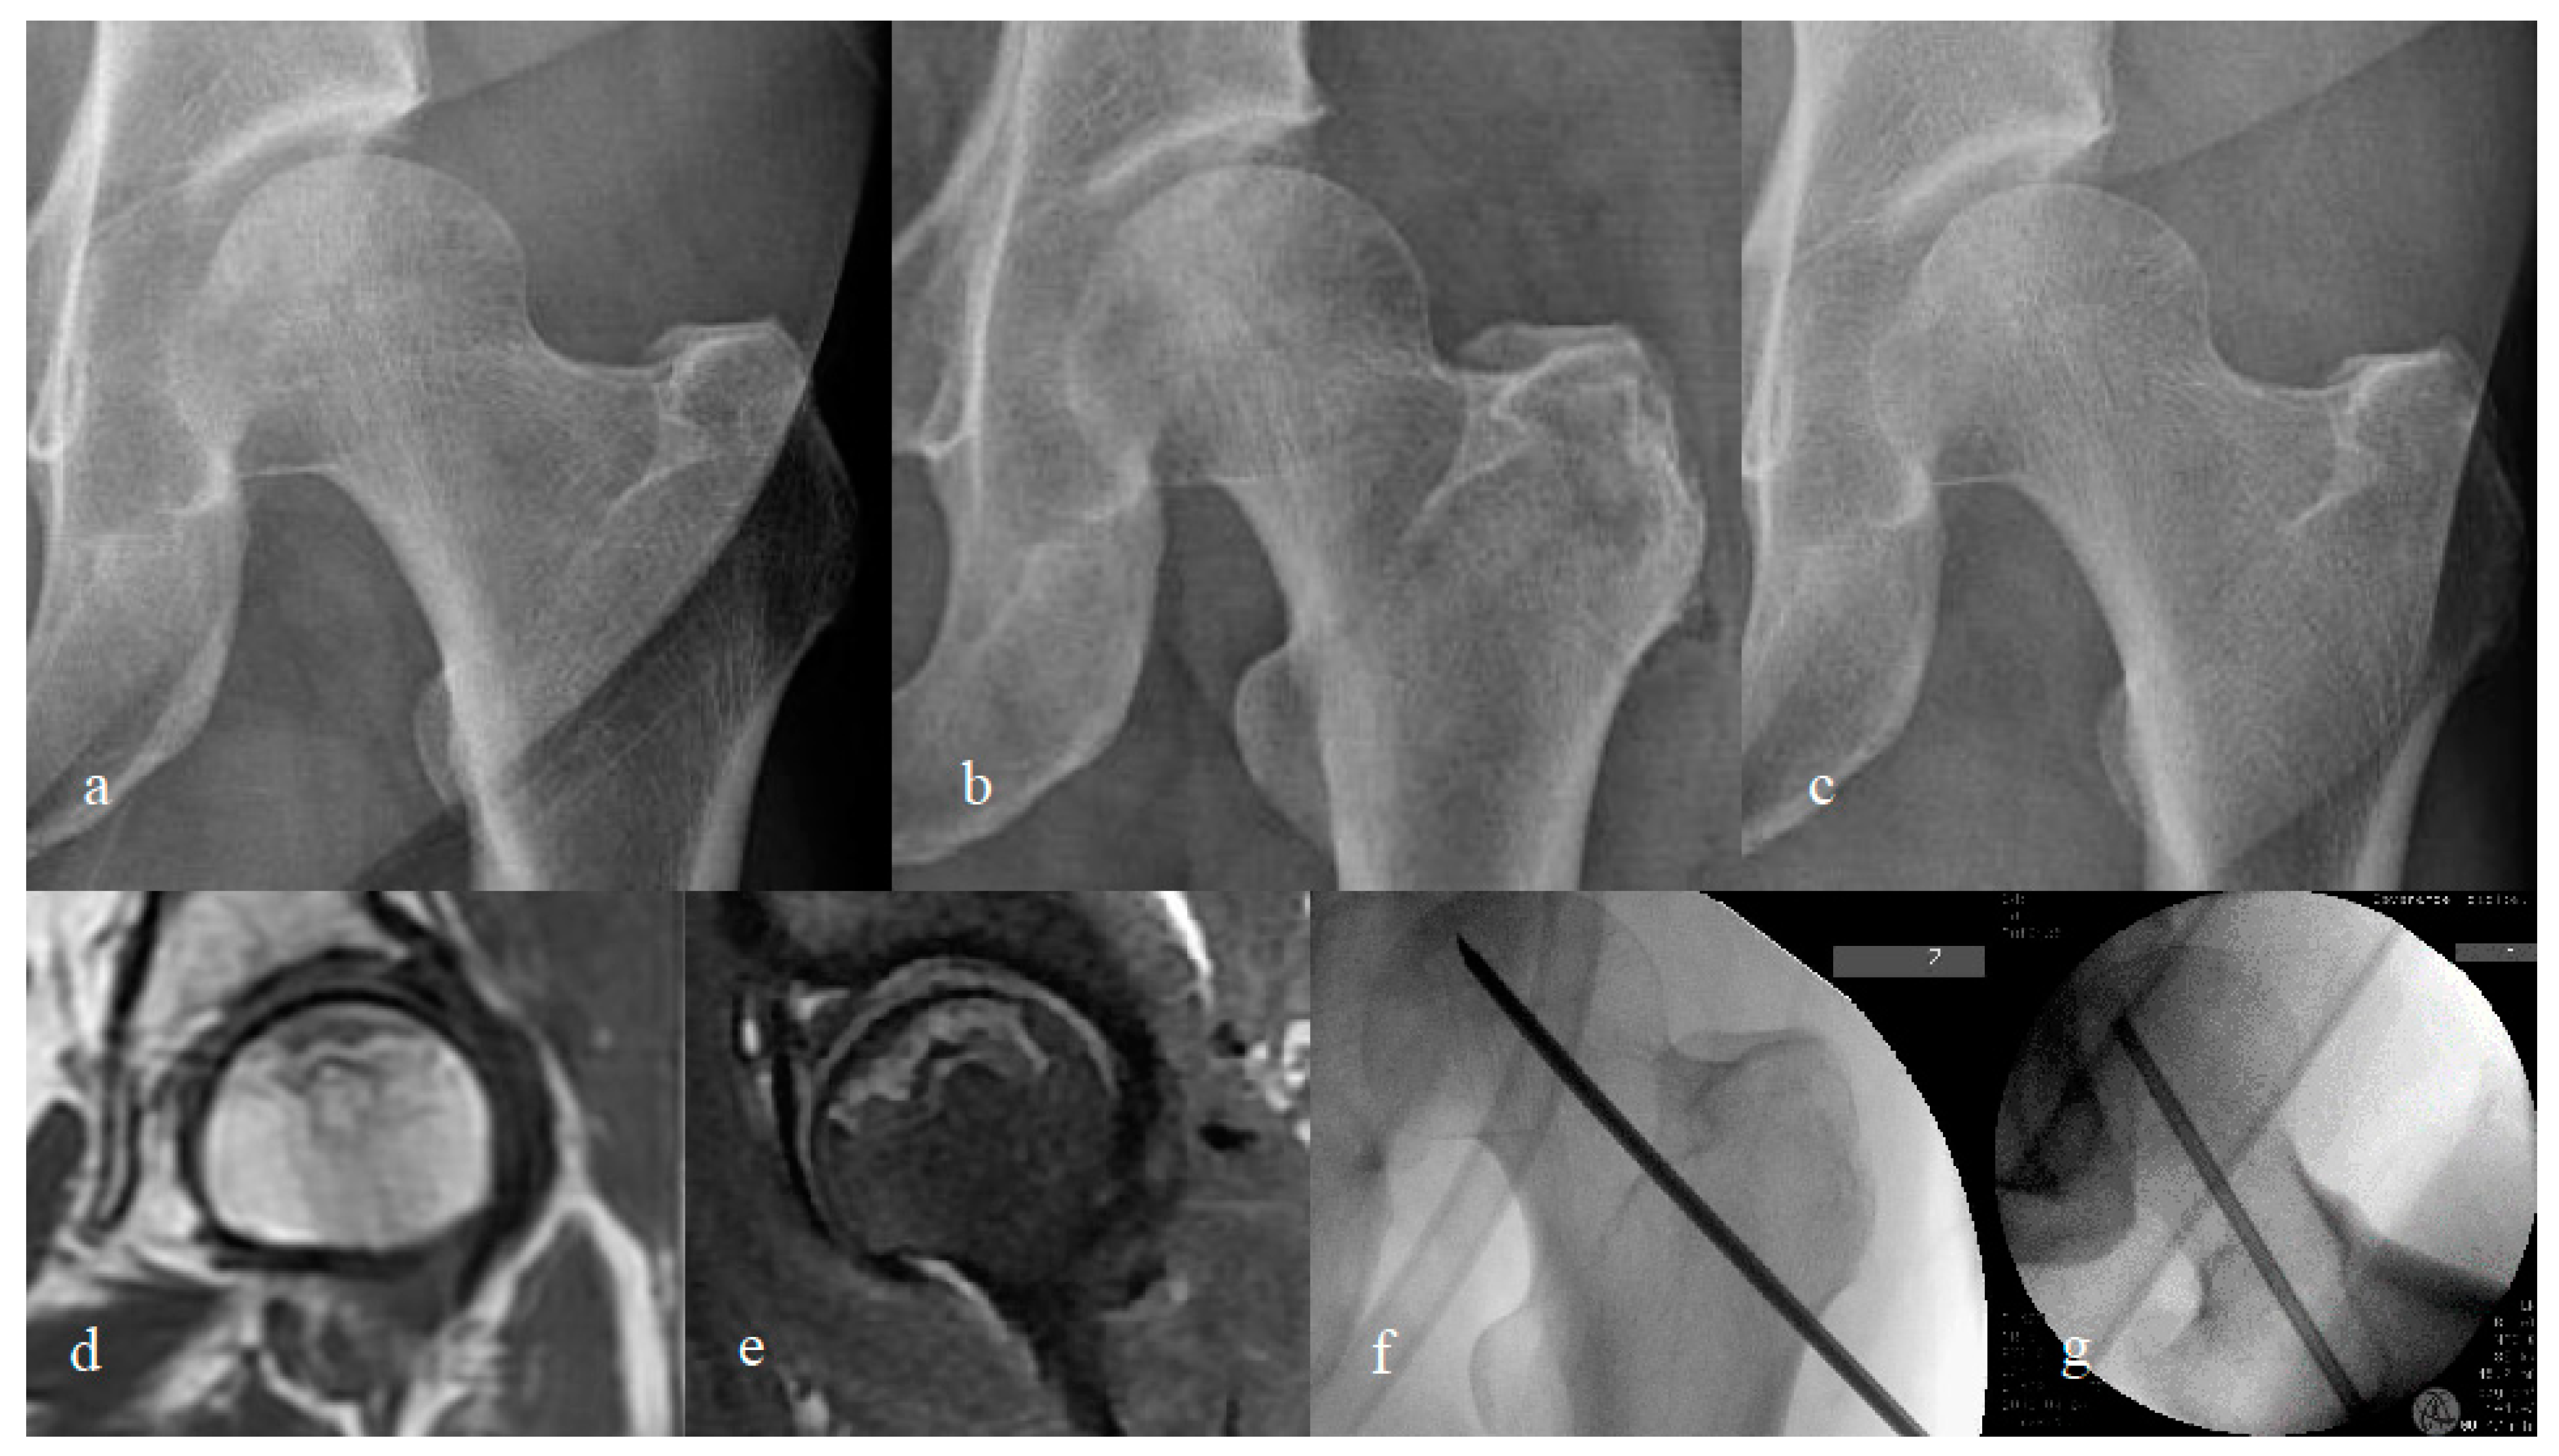

2.3. Trial Intervention